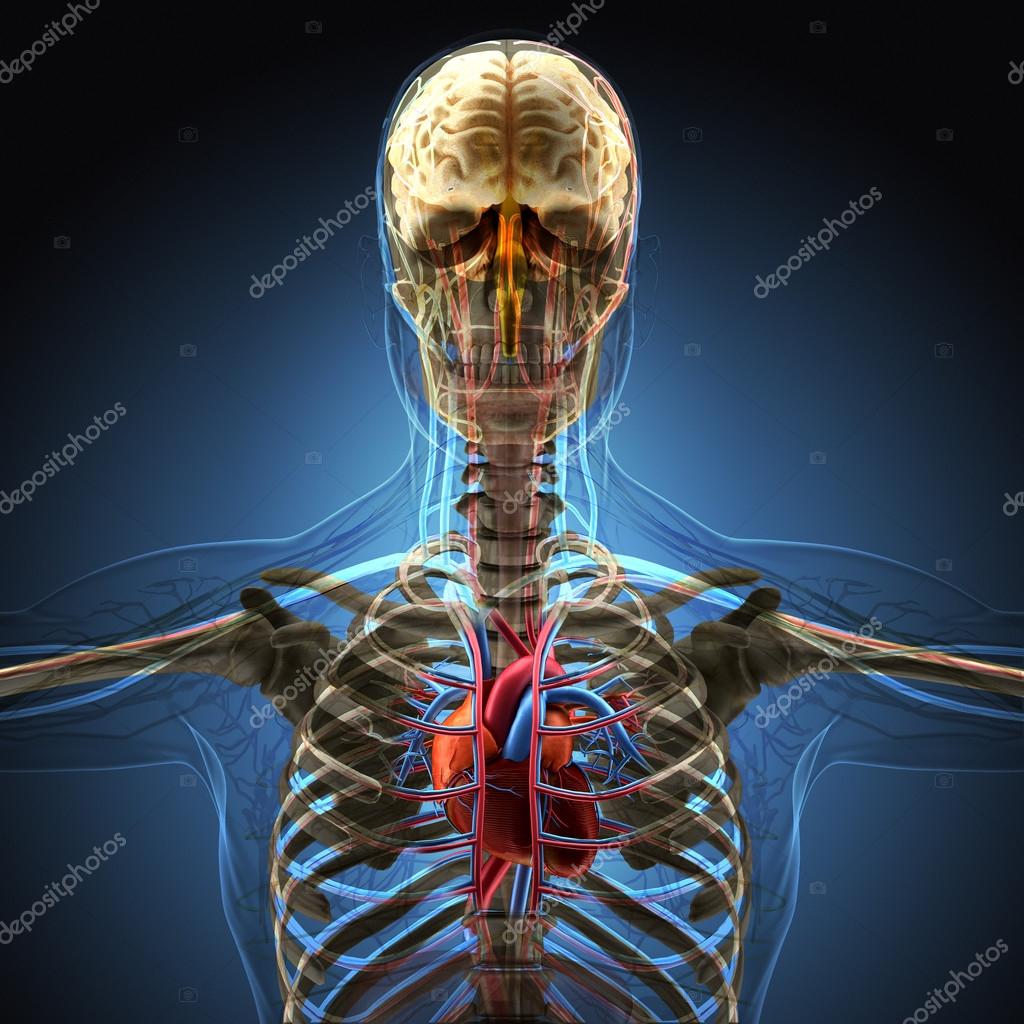

El Cuerpo Humano Por Rayos X Sobre Fondo Azul. 2025

www.deperu.com

www.deperu.com

Anatomía del cuerpo humano en vista de rayos x representación 3d. Cuerpo humano de rayos x con piel transparente representación. La imagen de rayos x del cuerpo humano fotografía de stock